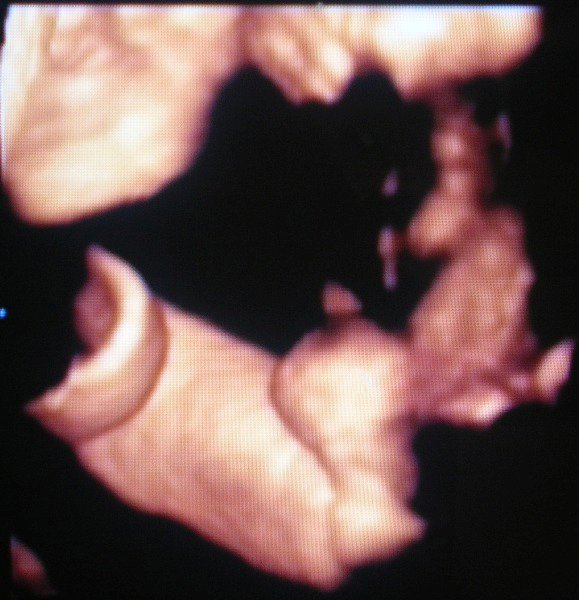

Bence 18 hetesen